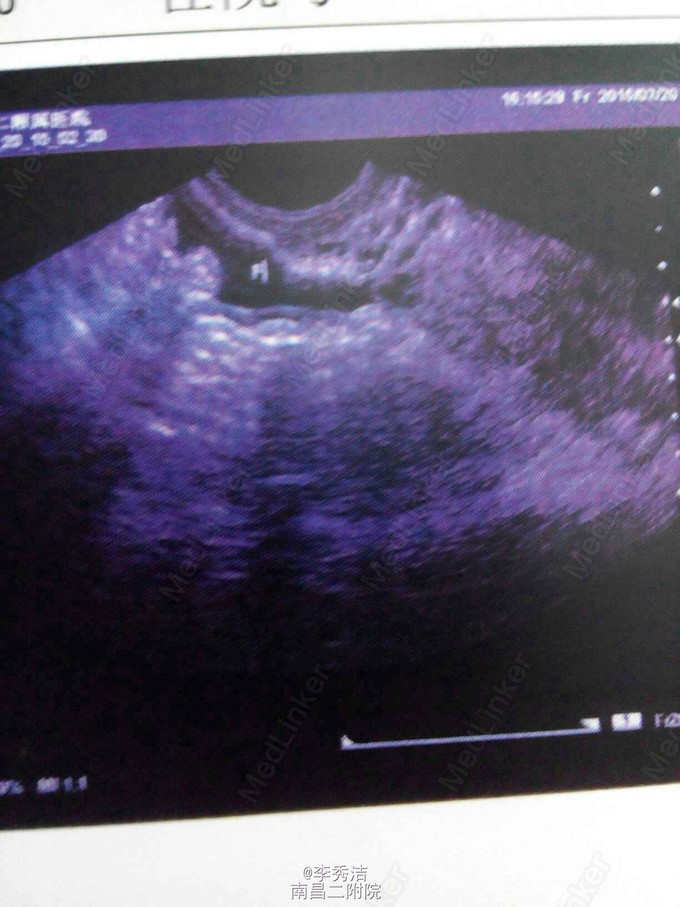

患者女,26岁,因“反复右下腹痛3月余,加重2天”入院。 患者自诉3月余前无明显诱因出现右下腹痛,无腹胀不适,与月经周期无明显关系,无阴道流血流液,半月前腹痛加重,伴阴道少量咖啡色分泌物,遂来我院门诊就诊,予以阿奇霉素点滴治疗4天,停药三天后再予以口服消炎药治疗后好转。现已停药2天,因右下腹痛再发,按压时明显,阵发性加重来我院门诊就诊,门诊拟“盆腔炎”收入住院,起病以来精神、食欲、睡眠可,大小便正常,体重无明显改变。既往体健,否认传染病史。无手术及外伤史,无输血史,无药敏史。平素月经规律,7天/37~45天,末次月经2015年2月9日,量中,暗红,有血块,白带量多,色黄,有臭味。已婚,G0P0,未避孕。 查体:生命体征平稳,心肺听诊未及异常,服平软,压痛明显。专科情况:外阴:已婚未产式,阴道:畅、软、少量淡黄色分泌物;宫颈:II度糜烂,举痛;宫体:前位,常大,压痛,右附件区压痛明显,左侧附件区未见明显异常。 辅助检查;今日我院妇科彩超示:右侧附件囊性暗区,考虑非赘生性囊可能性大,少量盆腔积液,子宫、右侧附件区未见明显异常。 诊断:盆腔炎 诊疗计划:1、行阴道分泌物培养+药敏,支原体培养+药敏,衣原体培养等检查。 2、因妇科感染多为G-、G+及厌氧菌感染,故给予其哌拉西林钠+奥硝唑静脉点滴抗炎治疗,待培养结果出来再行抗生素调整。